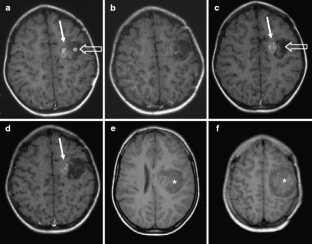

From a total of 61 DNTs, 48 simple and 13 complex variants were identified. Multiple or single pseudocysts in a cortical/subcortical location with small cysts sometimes separated from the tumor represented the glioneuronal element and were found in all DNTs. FLAIR hyperintense tissue was found between pseudocysts but—in neocortical DNTs—also circumscript in deeper tumor parts. Calcification and hemorrhages in this location occurred in four of 13 complex variants, and one of these patients was also the only one with tumor growth. Patients with complex variants had earlier seizure onset, and complex variants were more often located outside the temporal lobe. Although complex variants represented a higher diagnostic challenge, misdiagnoses also occurred in simple variants. One of five of DNTs showed contrast enhancement, which varied on follow-up studies with enhancing parts becoming nonenhancing and vice versa.